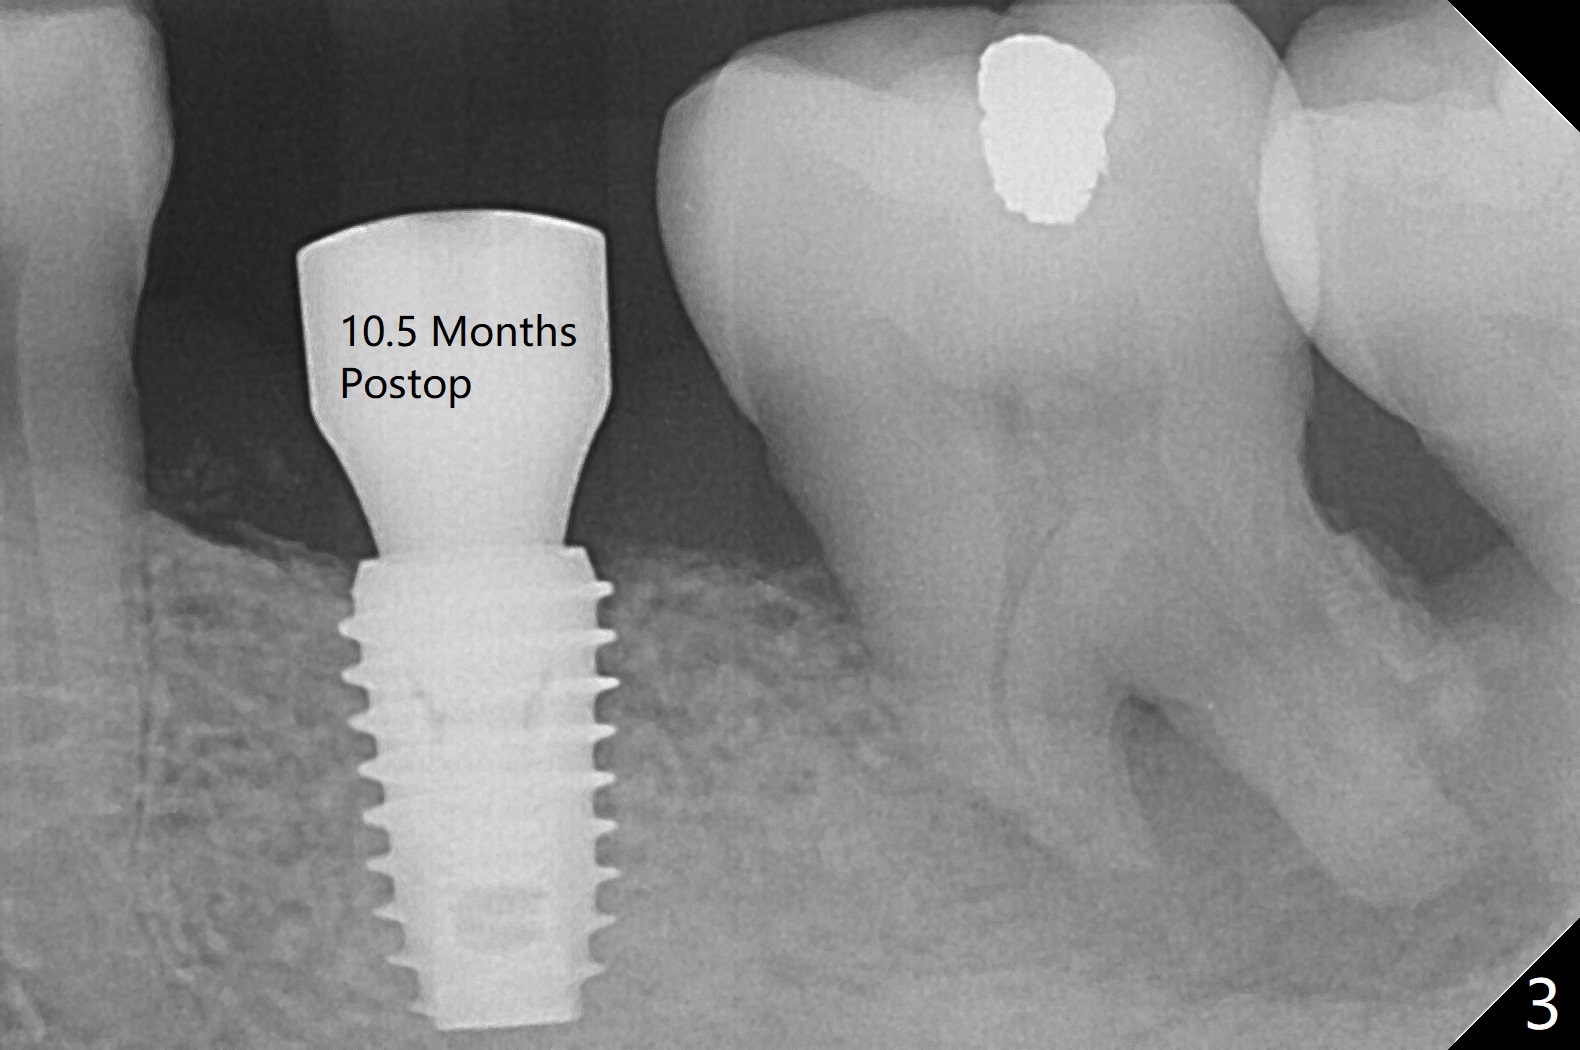

After use of 4.5x8.5 mm guide drill at #19, a 5x8.5 mm implant is placed with guide in place. When the latter is removed, the implant is found to be placed shallow. Following use of 4.5x10 mm drill for ~.75 mm deeper, the implant returns with deeper placement (Fig.1,2), confirmed after guide removal. The implant is further torqued 3 more times with visual confirmation of implant deeper placement. After seating a 5.5x5(3) mm healing abutment, autogenous bone graft is placed between the gingiva and the abutment to reduce chance of periimplantitis. The patient reports more severe pain (bone burn?) than free-hand placement at #30. In fact there is no bone loss around the implant 10.5 months postop (Fig.3).